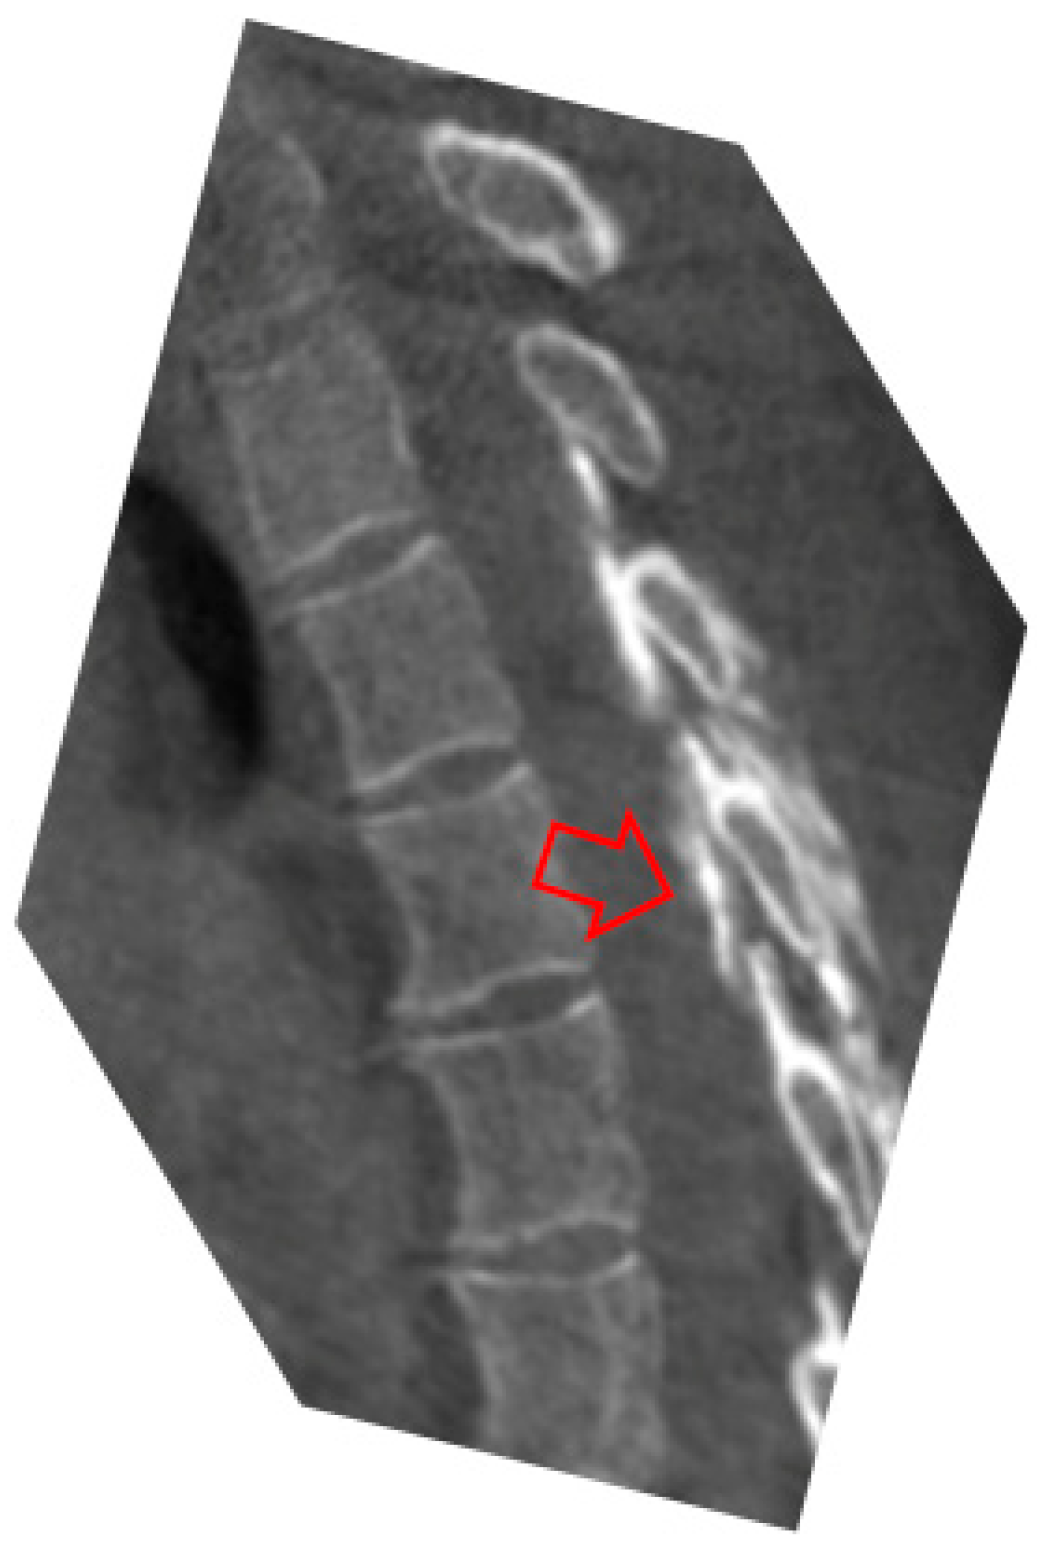

2. Case Report